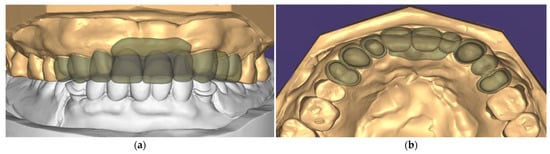

2. Case Description